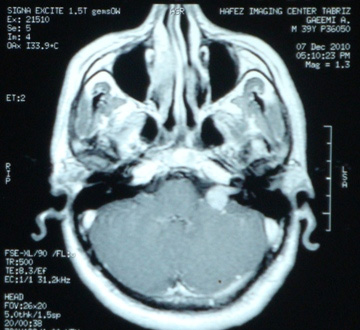

تومور در فضای بین مغز و گوش که زاویه پلی مخچه نامیده می شود، ایجاد می شود. آکوستیک نروما جزء تومورهای خوش خیم است اما خطر این تومور به دلیل رشد آن در فضای حساس و فشار آوردن آن به ساختارهای حیاتی مثل اعصاب جمجمه، مغز و ساقه مغز است. شایع ترین نشانه تومور شامل کاهش شنوائی در گوش مبتلا، وزوز گوش و عدم تعادل می باشد. برای بدست آوردن بهترین نتیجه، تشخیص صحیح به منظور انتخاب بهترین روش درمان در این اختلال ضروری است. برای تشخیص نورینوم آکوستیک انجام ام آر آی توصیه می شود. این روش تصویر برداری نه تنها به تشخیص کمک می کند بلکه وسعت و عوارض احتمال مانند هیدروسفالی را مشخص می کند.

نمونه های زیر MRI تعدادی از بیمارانی است که توسط دکتر اصغری جراحی شده اند: